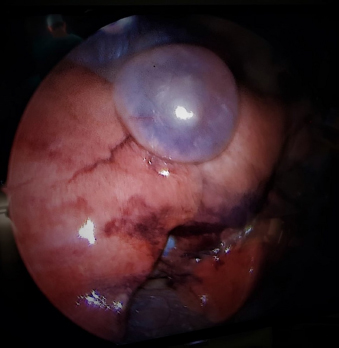

The right-sided chest tube was removed to allow for unrestricted inspection of the right thoracic cavity and to prevent potential interference with instrumentation during thoracoscopy in the small-sized patient. A skin incision was made at the level of the 4th intercostal space at the junction between the ventral and middle third of the thorax. Blunt dissection was performed until the pleura was perforated. A 5 mm endoscopic threaded shaft cannula with an open valve (Ternamian Endotip; Carl Storz Endoskope, Tuttlingen, Germany) was placed at the junction between the middle and the dorsal third of the 6th intercostal space. A 5 mm 30° fore oblique Hopkins endoscope (Carl Storz Endoskope, Tuttlingen, Germany) was used for exploration of the right thoracic cavity. Thoracoscopy confirmed the bulla within the right middle lung lobe (Fig. 5). No further pathological findings were detected on arthroscopic exploration.

Fig. 5. Thoracoscopic image of the right lung lobe. An air filled bullous structure with a thin membrane can be seen on the caudo-ventral aspect of the right medial lung lobe indicating a bulla. Thoracoscopic images corresponded with CT findings.